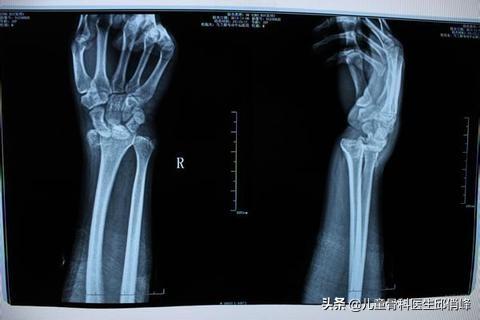

如果是持续疼痛,那要复查拍片,检查一下骨折是否愈合得好,或者复位得好不好,有些关节面没复位好,会持续产生摩擦,引起骨性关节炎。

有些是因为长短没恢复好,关节失去了平衡,导致持续性疼痛,很难恢复。

有些是骨折端错位,愈合后卡压了神经肌腱,引起其他组织慢性损伤,例如腕管综合征。